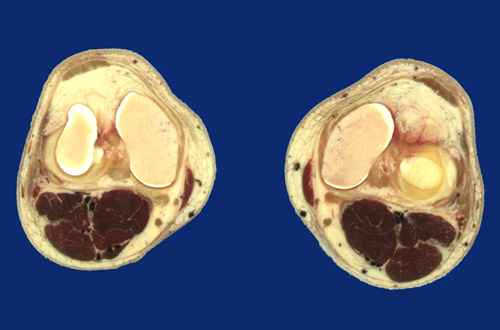

Identify the following regions in the image above: Popliteal vessels - Tibial nerve - Lateral meniscus - Anterior cruciate ligament - Posterior cruciate ligament - Patellar ligament - Infrapatellar fat pad - Medial femoral condyle - Sartorius - Semitendinosus tendon - Gastrocnemius, medial head - Gastrocnemius, lateral head - Plantaris - Popliteus - Iliotibial tract - Synovial space - Lateral meniscus